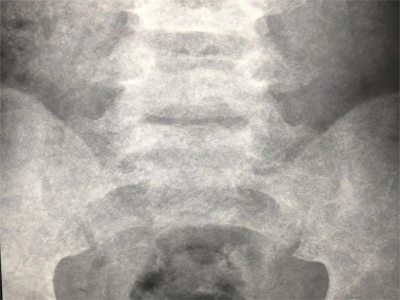

骶1隐性脊柱裂的图

骶1隐性脊柱裂主要是在身体发育的时候骶1的椎板未达到融合,在影像图上可以发现棘突缺如、椎板缺如的表现,需要通过手术进行治疗。